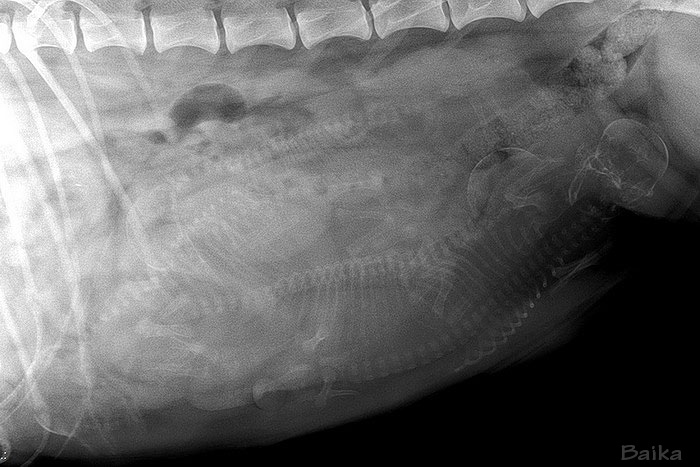

| Baika

Night

vom Reiterwappen HD-A2, CEA/PRA/Kat./Dist./MPP-frei, MDR1(+/+), DM-N/N, IPD N/N |

| Lajos | Baika |